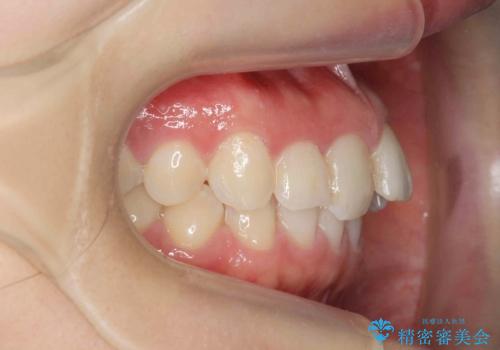

前歯のガタつきをきれいに マウスピース矯正治療

- 「前歯のガタつきをきれいにしたい。」と矯正治療を希望され来院されました。

前歯のガタつきをワイヤー部分矯正、上顎前突の咬合関係を後方移動することで理想的な咬合関係を確立します。

上顎の全体的な後方移動を実現するためにマイクロインプラントを併用したゴムかけを行ったことで理想的な咬合関係を確立することができました。